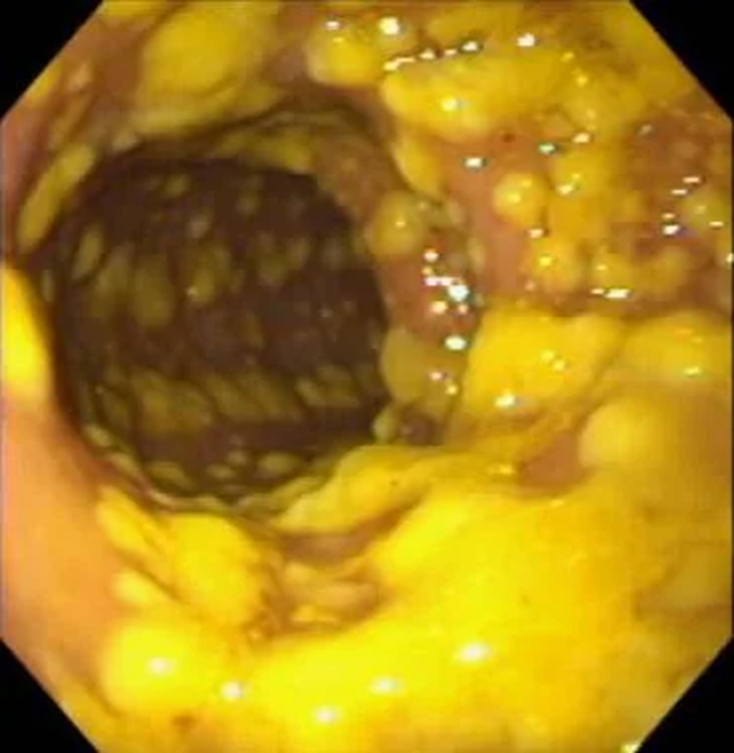

Заболевание, которое развивается, так и названо — С. difficile-инфекция, однако во многих случаях используют еще один термин — псевдомембранозный колит, который отражает картину, наблюдаемую на слизистой кишечника у больного: появление наложений фибрина — псевдомембран (рис. 3).

Рисунок 3. Эндоскопическая картина множественных псевдомембран на слизистой толстой кишки при C. difficile-инфекции.